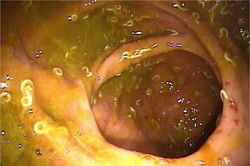

![]() gonorrea |